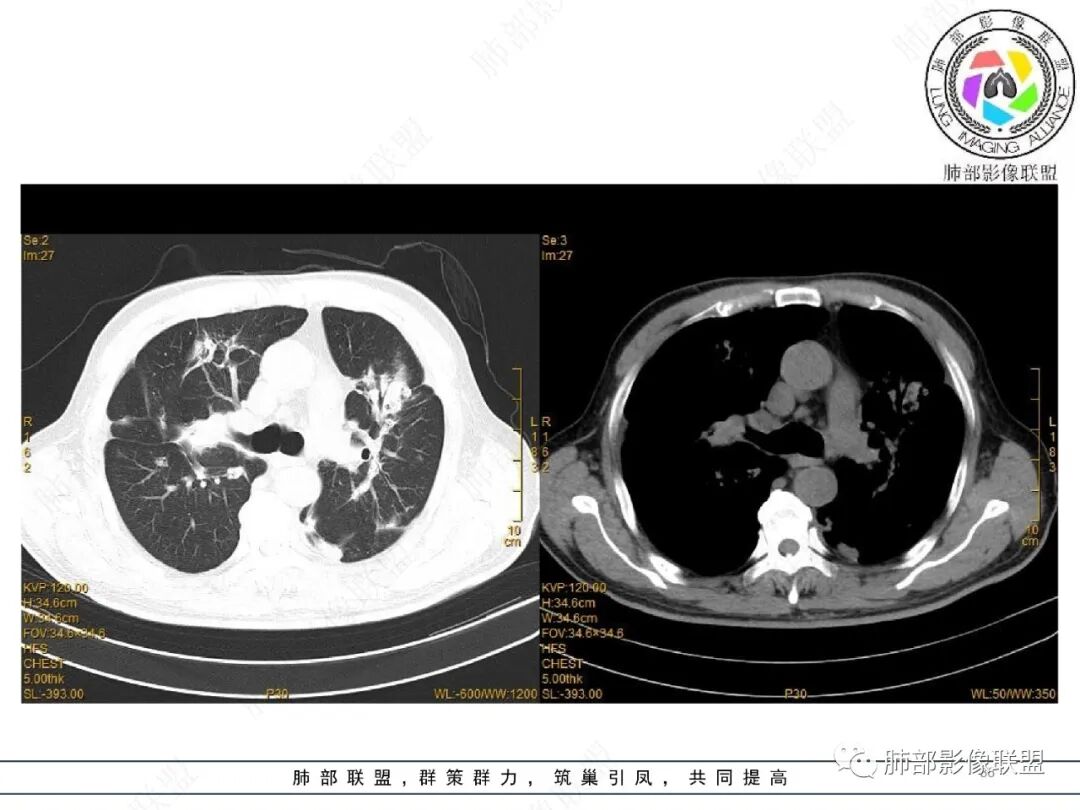

2022.2.17CT显示两肺中内带多发结节影、斑片影、条索影,部分病灶侧向融合与胸膜平行。部分病灶沿着支气管血管束分布、其内支气管稍扩张。部分病灶呈反晕征。大部分病灶边界显示清晰,部分病灶周围可见边界不清的GGO。2022.4.12CT显示两肺中内带多发结节影、条索状、条带状高密度影,边界收缩平直凹陷,大部分病灶沿着支气管血管束分布,亦有位于胸膜下侧向融合与胸膜平行的病灶。总体与第一次CT对比两肺病灶明显吸收。